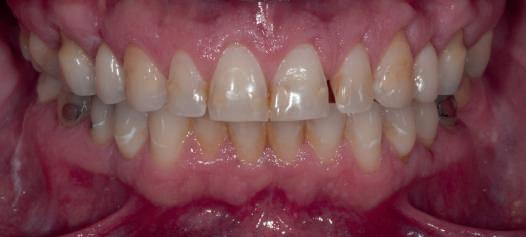

locaţii grefate. Implanturile plasate în această primă fază au fost încărcate cu bonturi conice şi, în unele cazuri, cu omologii lor angulaţi (fig. 16, 17).

S-au selectat bonturi standard de titan pentru a evita schimbarea sau refrezarea bonturilor individualizate mai scumpe; în plus nu necesită utilizarea cimentului temporar în proximitatea sau în jurul locaţiilor chirurgicale, întrucât utilizează doar şuruburi pentru retenţie.

Atitudine: Până la dobândirea vindecării totale a ţesuturilor şi a implanturilor secundare s-au utilizat bonturi standard de titan. Fig. 18 prezintă bonturile individualizate maxilare şi mandibulare aplicate iar fig. 19 un prim-plan al cadranelor de partea dreaptă a pacientului, afişând finalizarea cazului la 15 luni după începerea tratamentului iniţial. Recesiile se pot obiectiva corespunzător 1.4. şi 1.3. În acest caz, s-a încercat minimizarea susceptibilităţii la recesie prin implicarea bonturilor temporare standard fixate cu şurub în cursul fazelor de vindecare pe toată durata etapelor iniţiale ale tratamentului.

În pofida acestor eforturi, totuşi, recesia a apărut în anumite regiuni unde implanturile erau plasate vestibular. Ulterior, s-a încercat grefarea ţesutui moale din jurul locaţiilor cu recesie, dar fără succes.

Cazul (5):

Bonturi conice utilizate ca bonturi temporare

Figurile

16, 17. Implanturile din prima etapă încărcate cu bonturi conice şi, în unele cazuri, omologii angulaţi.

18. Bonturile individualizate inserate.

19. Rezultat final la 15 luni după începerea tratamentului iniţial.

şi va induce resorbţie osoasă şi migraţia apicală a ţesutului (Saadoun & Touati). Dacă implantul nu este plasat mai palatinal şi la 3-4mm apical de marginea gingivală liberă pentru a asigura profilul de emergenţă adecvat, rezultatul estetic este compromis (Chu et al). Un studiu de 2 ani a demonstrat că implanturile poziţionate anterior au demonstrat o recesie uşor mai accentuată, decât implanturile posterioare (Bengazi et al). Plasarea vestibulară a implanturilor se poate vizualiza clar în cazul 5 (fig. 17) cu bonturile de vindecare în poziţie.

Proximitatea implanturilor adiacente

Se recomandă existenţa a cel puţin 3mm de os între două implanturi adiacente (Tarnow et al). În acelaşi caz 5, corespunzător 2.5. şi 2.6. distanţa la nivel inter-implantar este sub 2mm iar între bonturi sub 1mm (fig. 17). Întrucât ţesuturile inter-implantare nu au acelaşi nivel de suport ca în cazul dinţilor naturali, distanţa interdentară devine esenţială în anticiparea poziţiilor finale ale ţesutului moale.